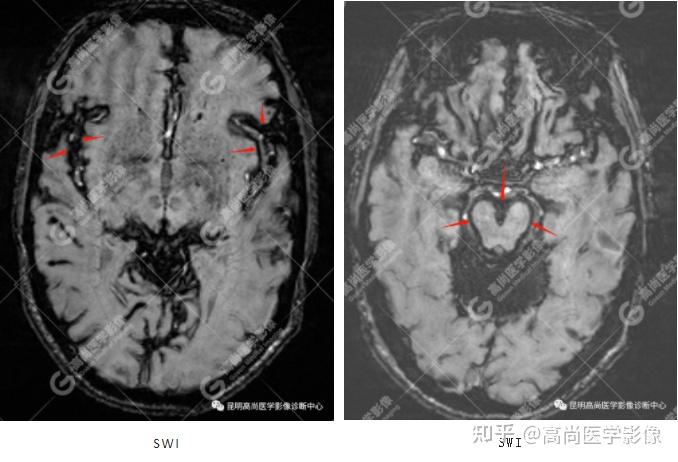

言语困难,表述不清,确诊:中枢神经系统表面铁质沉积症,伴轻度小脑萎缩

脑组织铁沉积神经变性病临床与影像诊断(二)